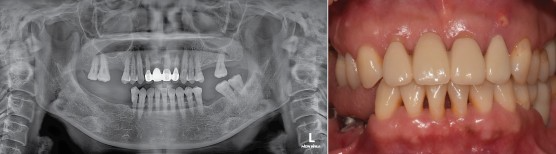

#21.22 신경치료 진행 / 마무리